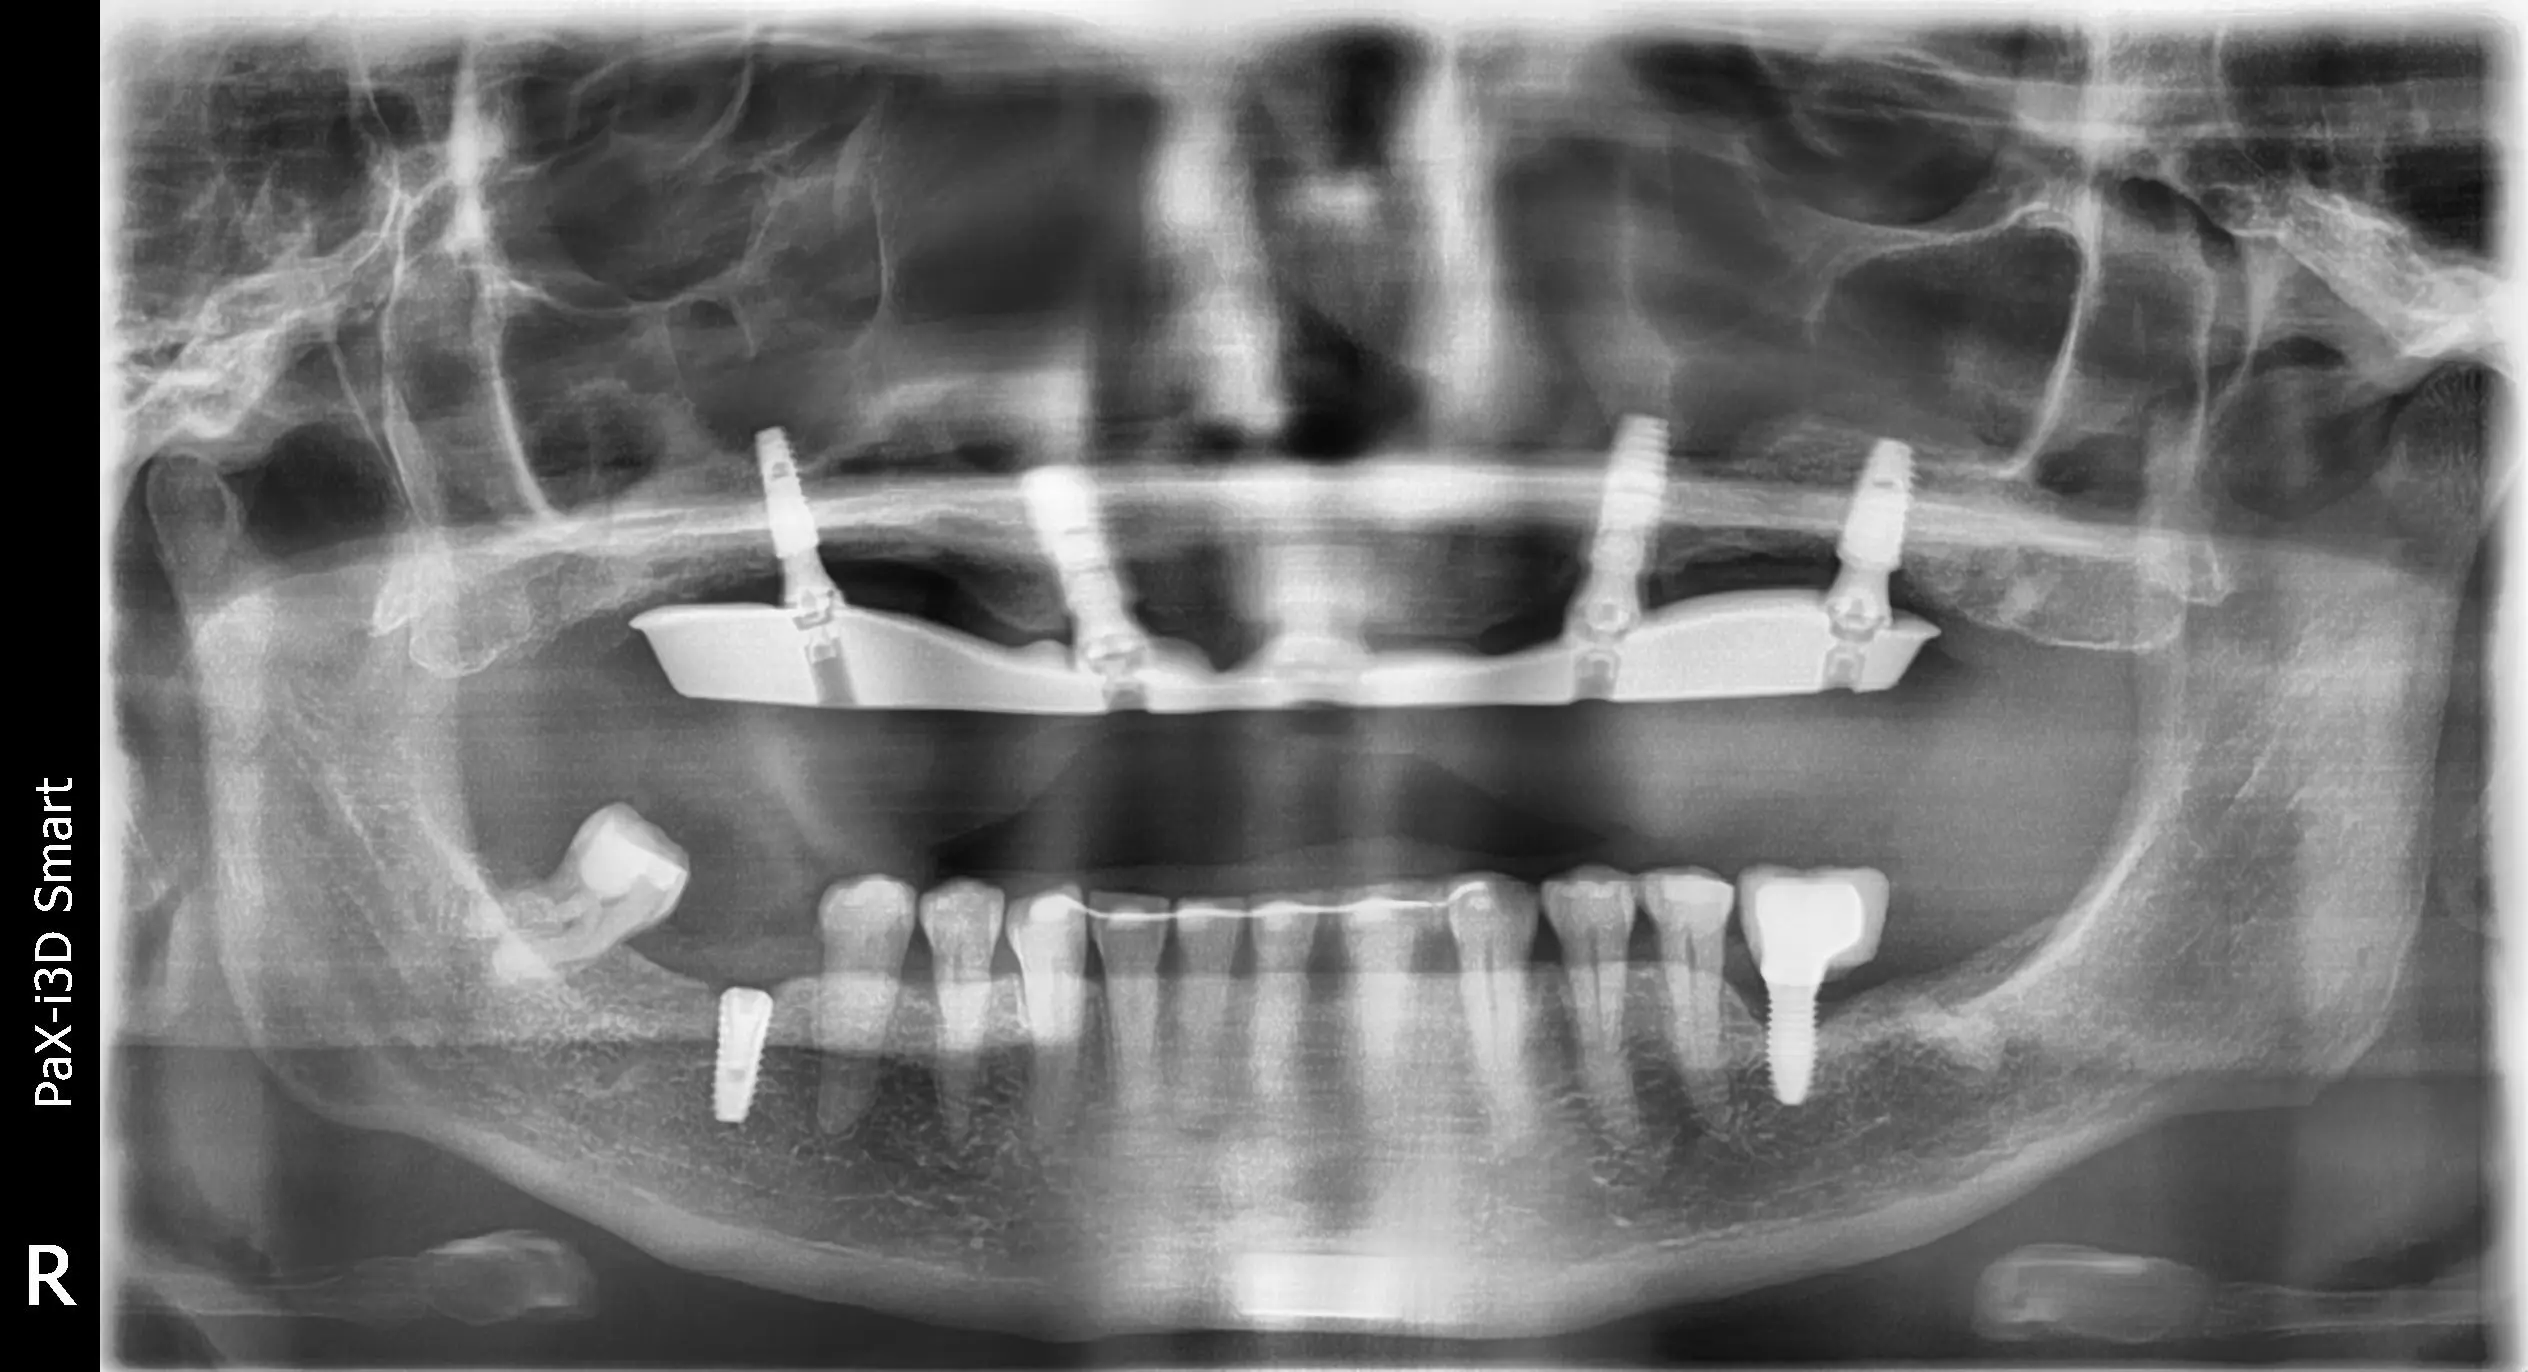

Diagnóstico Diagnóstico

1. Gran pérdida ósea

2. Inflamación de encías

3. Mordida incorrecta

4. Movimientos dentarios

Prótesis fija de cerámica y titanio sobre 5 implantes en el maxilar superior

Colocación de implantes dentales